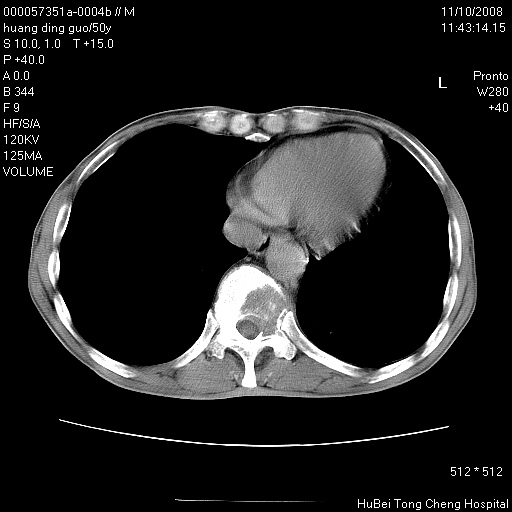

患者 男,50岁。左侧腰背部疼痛3月余,伴消瘦。平素健康,无传染病史。

胸部ct轴位平扫(层厚10mm,螺距1.5,重建间隔10mm),图像如下:

左肺下叶背段有一厚壁空洞,外壁呈锯齿状伴毛刺改变。空洞相邻胸膜有牵拉改变。左肺下叶血管支气管束不规则增粗,小叶间隔增厚。胸椎骨质破坏。考虑左肺下叶周围型肺癌伴左肺下叶癌性淋巴管炎、胸椎转移。

左肺下叶背段有一厚壁空洞,外壁呈锯齿状伴毛刺改变。空洞相邻胸膜有牵拉改变。左肺下叶血管支气管束不规则增粗,小叶间隔增厚。胸椎骨质破坏。考虑左肺下叶周围型肺癌伴阻塞性肺炎、胸椎转移。其他待排

左肺下叶背段有一厚壁空洞,内壁不规则,外壁呈锯齿状伴毛刺改变。空洞相邻胸膜有牵拉改变。周围呈絮状炎性改变,左肺下叶血管支气管束不规则增粗,小叶间隔增厚。胸椎骨质破坏。考虑左肺下叶周围型肺癌伴左肺下叶阻塞性肺炎、胸椎转移。